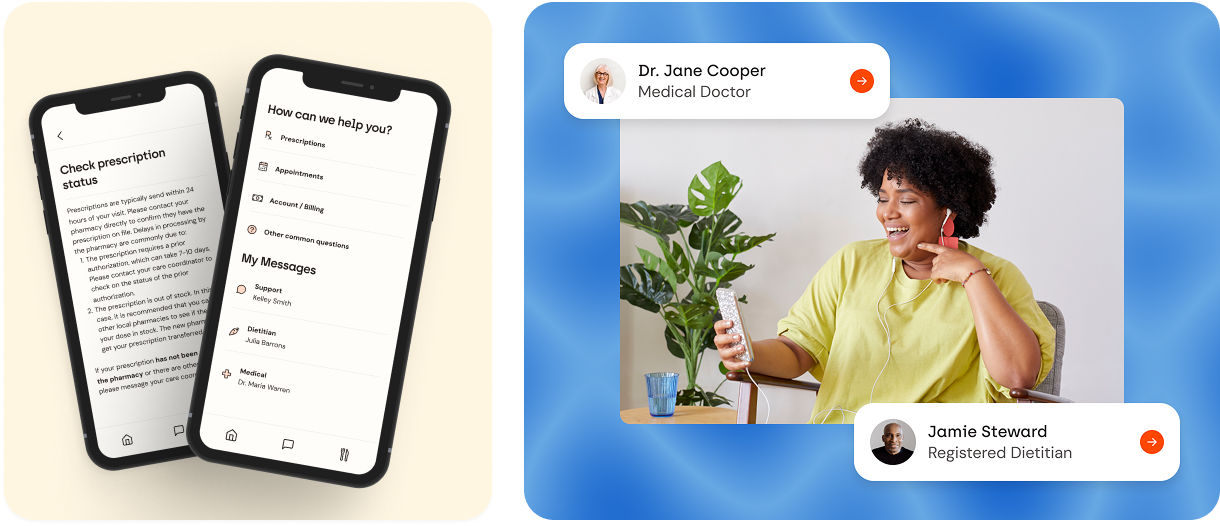

Patient Messaging & Routing

COMPANY

Form Health

ROLE

Lead Product Designer

PROJECT

Improved Form Health's in-app chat system to efficiently route patient questions, reduce redundant messages, and free up clinician time.